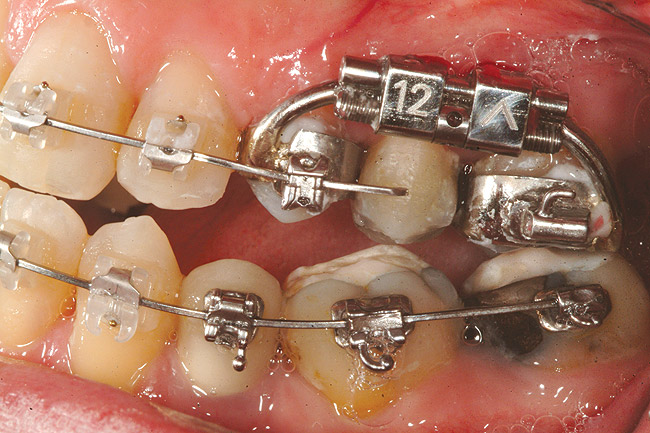

Fig 24 (through Fig 26). A 50-year-old female concerned about appearance and bite. Jackscrew appliance was placed after 6 months of orthodontic alignment.

Figure 24

Fig 25. A 50-year-old female concerned about appearance and bite. Jackscrew appliance was placed after 6 months of orthodontic alignment.

Figure 25

Fig 26. A 50-year-old female concerned about appearance and bite. Jackscrew appliance was placed after 6 months of orthodontic alignment.

Figure 26

Fig 27. Patient was missing tooth No. 11 and had A-P and transverse maxillary deficiencies with anterior and left posterior crossbites. Bite was opened with glass ionomer cement. Single-tooth osteotomies were performed on teeth Nos. 6 and 12 and multiple-tooth osteotomies were completed on teeth Nos. 3 to 4, 7 to 10, and 13 to 14.

Figure 27

Fig 28. Corticotomies were also performed on Nos. 7 to 10 segment. Postsurgery 21 days.

Figure 28